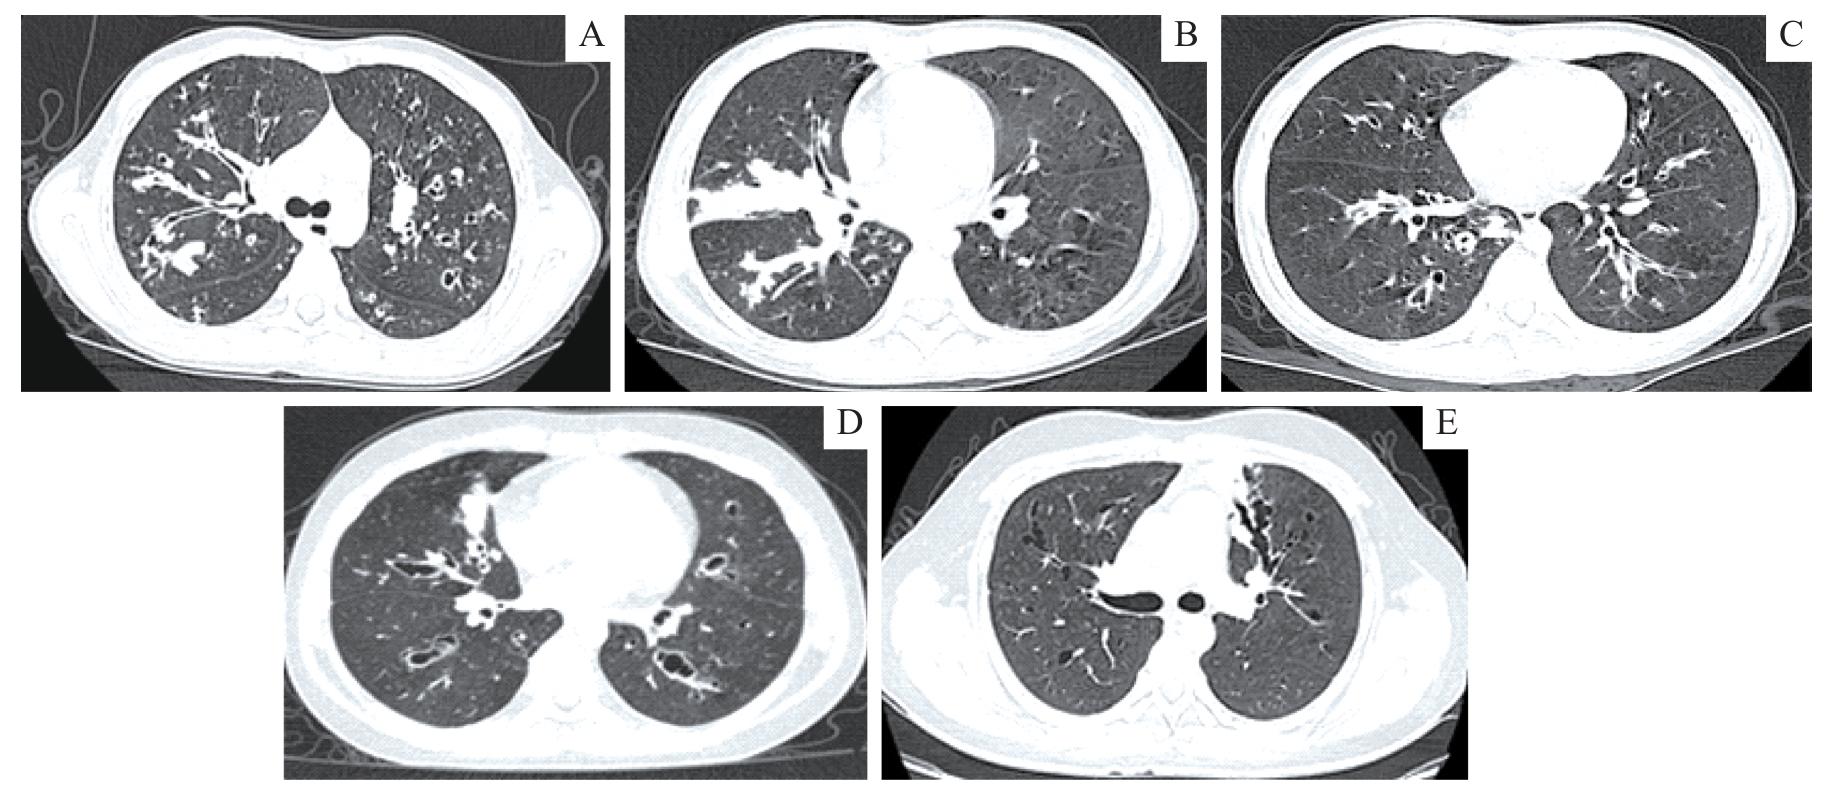

孙雅, 安云霞, 武旋, 等. 囊性纤维化并发变应性支气管肺曲霉病1例报告及文献复习[J]. 国际呼吸杂志, 2023, 43(1): 106-11.SUN Y, AN Y X, WU X, et al. Cystic fibrosis complicated with allergic bronchopulmonary aspergillosis: A case report and literature review[J] Int J Respir, 2023, 43(1): 106-111.